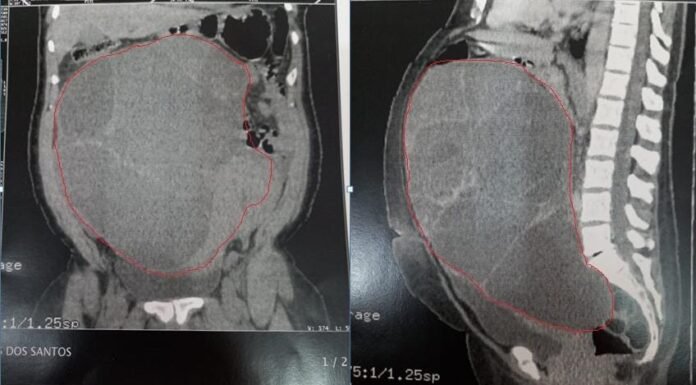

A servidora pública Silvia Nunes dos Santos, de 47 anos, aguarda há sete meses por uma cirurgia para remoção de um cisto no Hospital Geral de Roraima (HGR). A situação foi denunciada na tarde de hoje (4).

Conforme a irmã da paciente, Simone Nunes, de 44, o cisto fica na região do abdômen e...